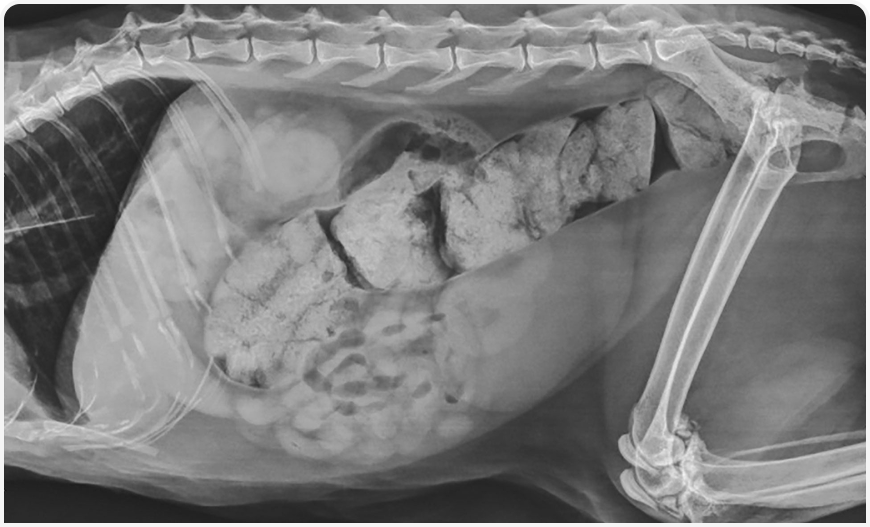

Распространенность запоров, связанных с ХБП у кошек, в литературе не описана, но, по-видимому, она достаточно высока (Рисунок 6). Предварительные результаты исследования характерных особенностей дефекации у кошек свидетельствуют, что при ХБП дефекация менее регулярная, и запоры, вероятно, обусловлены нарушением водного баланса и, возможно, перистальтики желудочно-кишечного тракта. Поскольку почки не могут надлежащим образом концентрировать мочу и организм борется с хроническим субклиническим обезвоживанием, из толстой кишки компенсаторно реабсорбируется вода. Также возникновению запоров могут способствовать гипокалиемия и применение фосфат-связывающих препаратов (24, 25). Терапия запоров заключается в коррекции обезвоживания и электролитного дисбаланса, увеличении содержания клетчатки в диете, применении специальных кормов, осмотических размягчителей стула или стимуляторов моторики кишечника, например лактулозы. Запор может вызывать и другие негативные клинические последствия; вероятно, его можно считать классическим примером функционирования оси кишечник — почки. Как упоминалось ранее, у пациентов с ХБП при запорах концентрация уремических токсинов выше, чем у пациентов с нормальной балльной оценкой фекалий, и наоборот, эти токсины могут отрицательно воздействовать на перистальтику желудочно-кишечного тракта (8). При лабораторном моделировании ХБП было продемонстрировано значительное снижение уровня уремических токсинов, креатинина и даже гистопатологических изменений в почках после приема лактулозы (26).